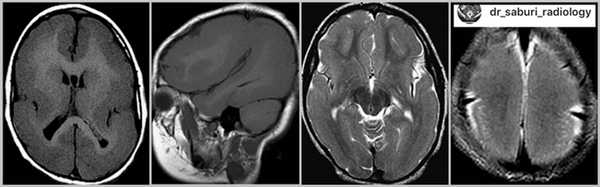

- КТ головного мозга. При компьютерной томографии определяются широко расставленные передние рога, высокое стояние третьего желудочка, параллельный ход медиальных стенок боковых желудочков. КТ производится в рамках постнатальной диагностики.

- МРТ головного мозга. Для максимально точной визуализации степени агенезии или гипоплазии мозолистого тела новорожденным выполняется магнитно-резонансная томография в трех плоскостях. По показаниям МРТ может рекомендоваться беременным женщинам для исключения несовместимых с жизнью сочетанных пороков ЦНС.